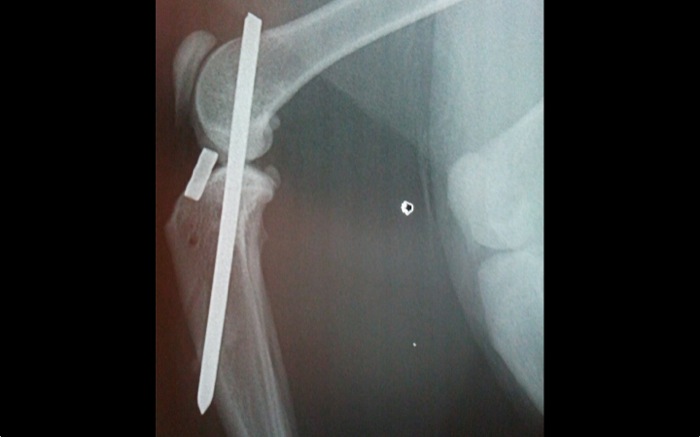

| Pruebas | La radiografía expone una amplia luxación femoro-tibial sin fracturas aunque con una gran inflamación de rodilla. La cápsula parece íntegra. El ligamento cruzado caudal está roto pero el craneal no es valorable. Obviamente en este caso hay grandes limitaciones para la exploración incluso bajo anestesia. |

La radiografía tomada de urgencias con el animal despierto apunta hacia una lesión grave aunque poco clara sobre todo por lo infrecuente de la lesión.

Una vez limpia la articulación de coágulos, fibrina, restos de ambos ligamentos cruzados y meniscos se implanta un clavo centrado y encima del surco rotuliano. El lugar de salida es exactamente en el origen del ligamento cruzado craneal para entrar posteriormente en la meseta tibial donde este ligamento debiera insertarse.

La artrodesis o anclaje articular temporal queda en la posición esperada en un segundo intento. Se realizó previamente una prueba con una aguja de Kirshner de pequeño calibre pero la dirección de salida no era idónea. Sí en un nuevo intento saliendo distal y por el centro de la cresta tibial.